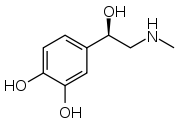

- Noradrengeric (Norepinephrine and normetanephrine)

Structure of norepinephrine

Structure of norepinephrine- More likely to indicate an extra-adrenal tumor[74]

- Patients are more likely to present with continuous, persistent pheochromocytoma-related symptoms (hypertension and tachycardia) compared to those that are classically episode with an adrenergic phenotype[62]

- Common in patients with von-Hippel Lindau and succinate dehydrogenase subunit X genetic variants[62]